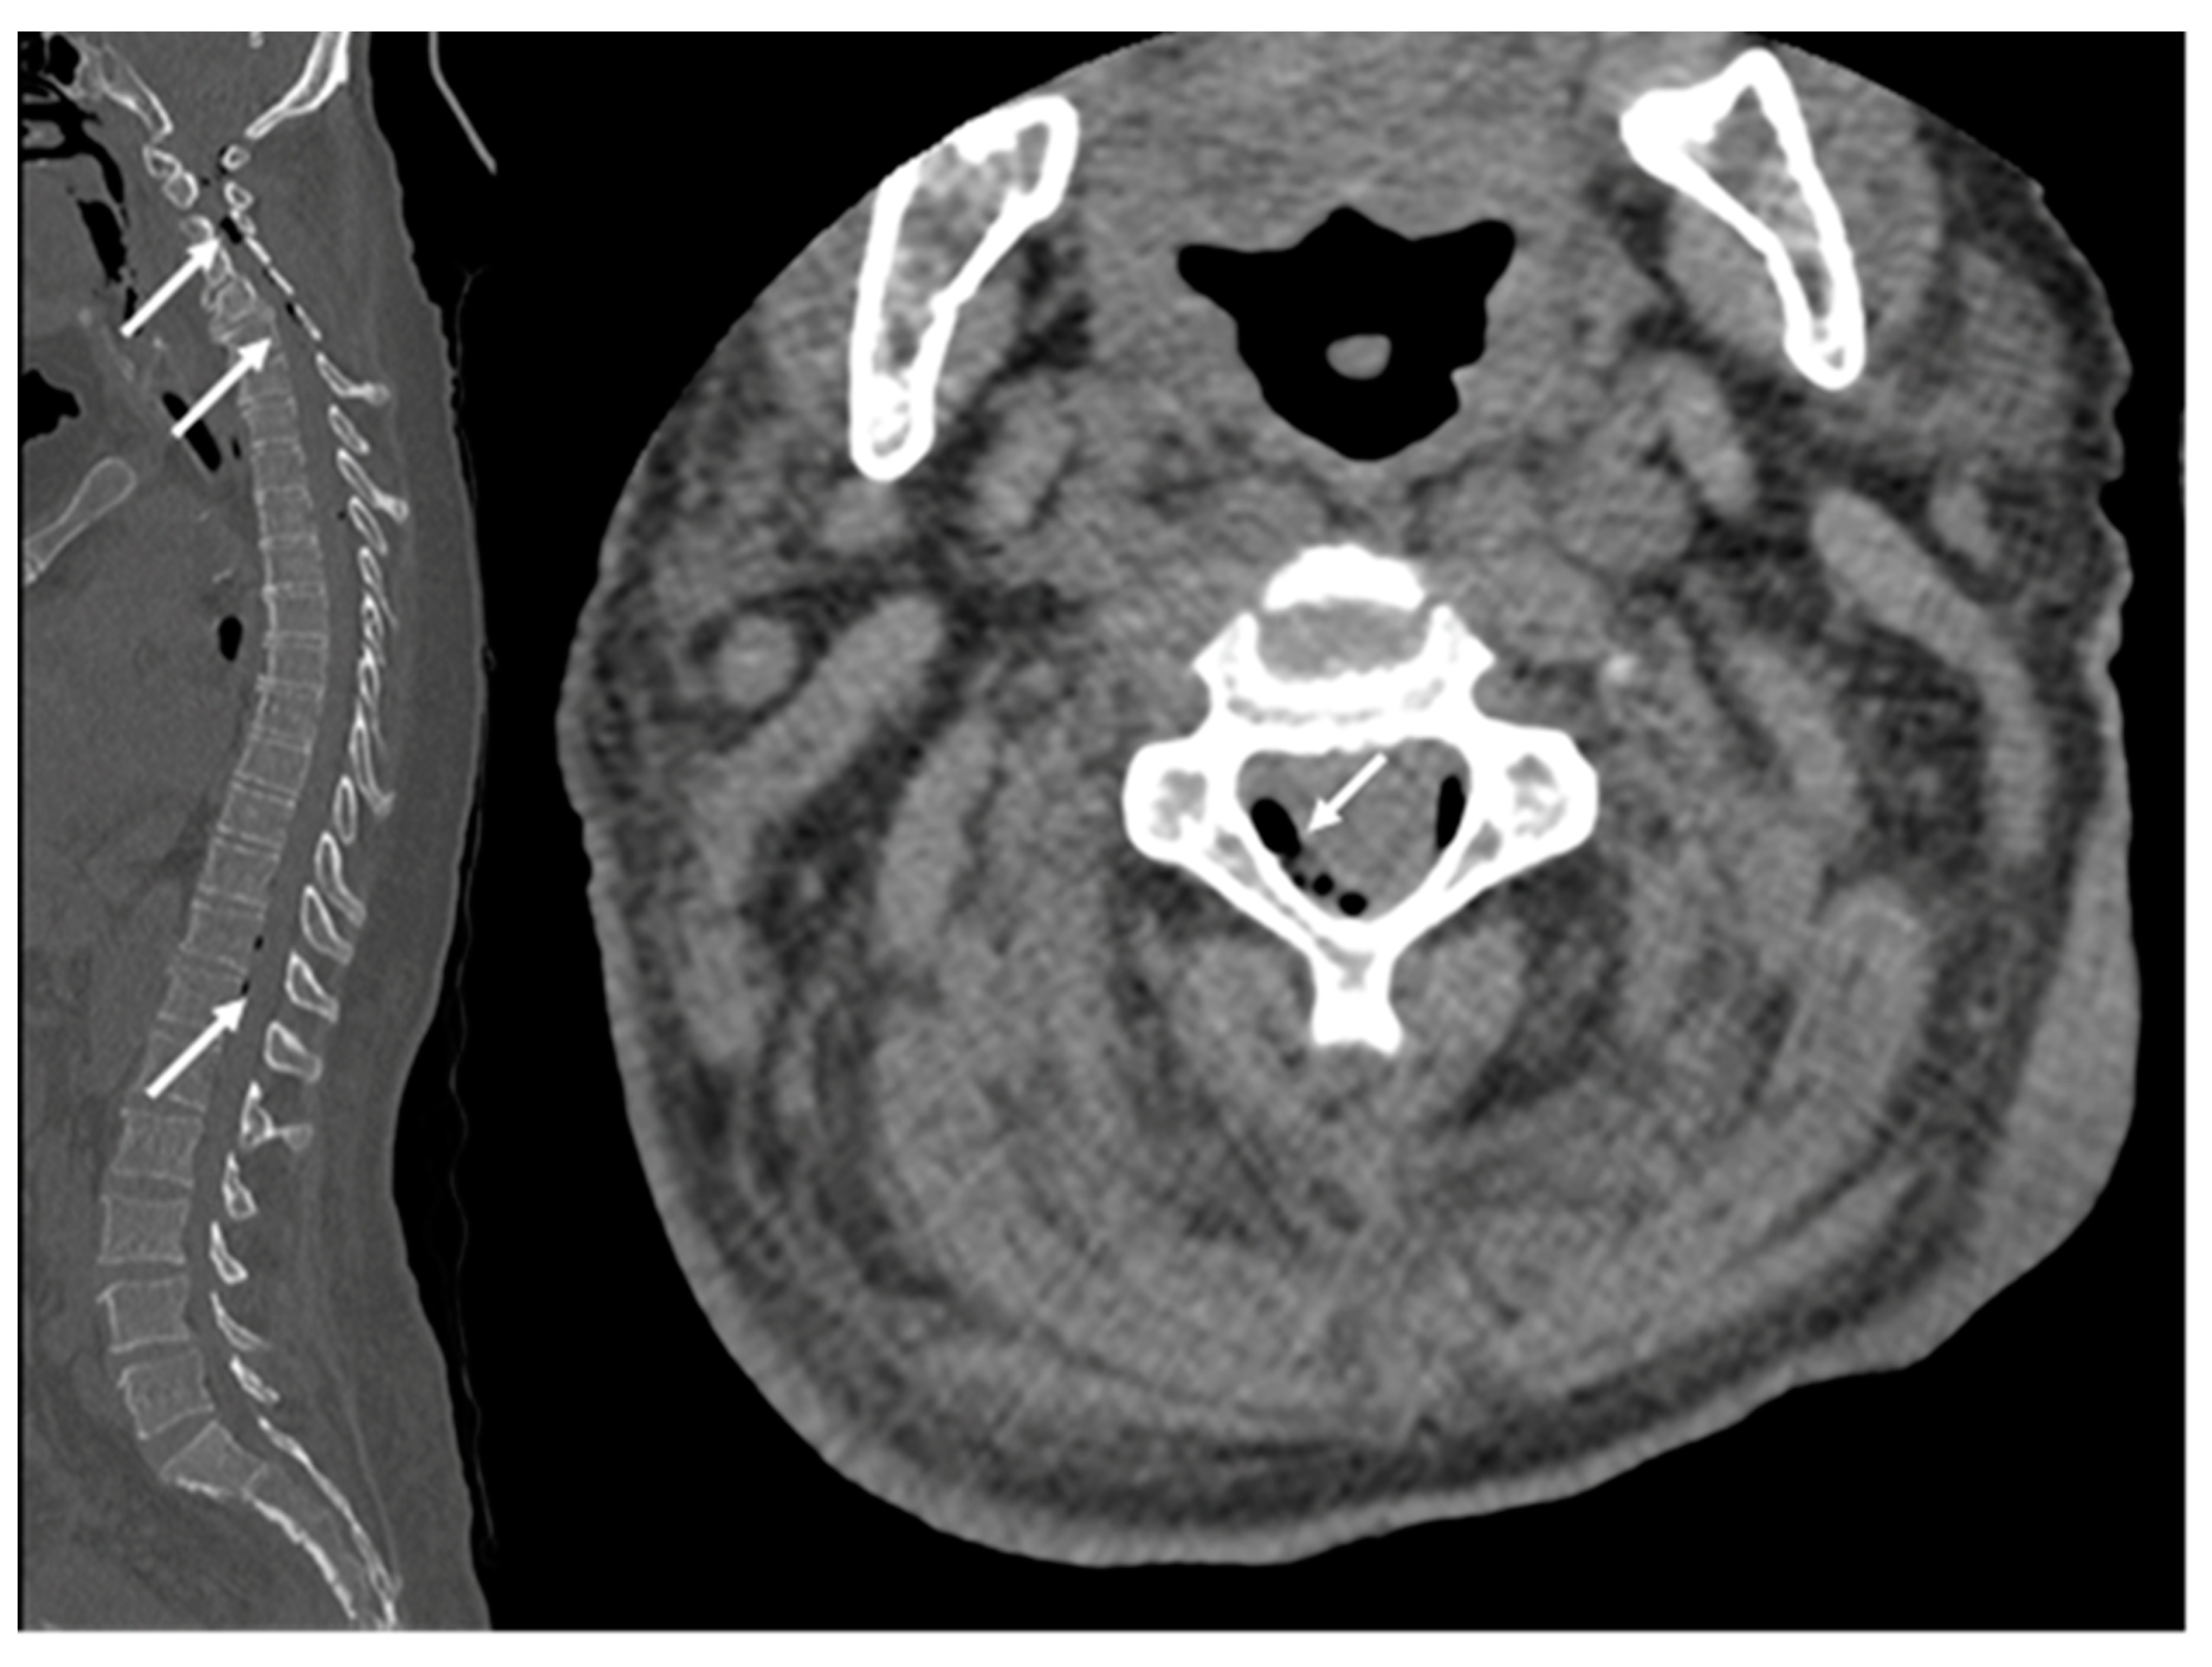

2.1. Case Report